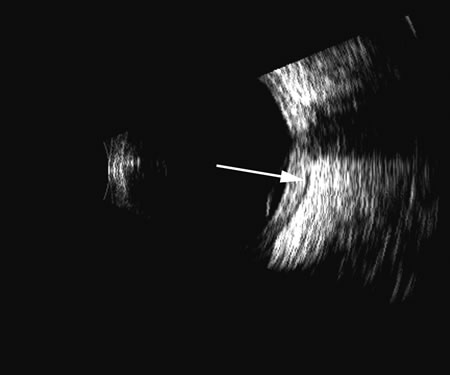

Fig. 12. Scleritis of the posterior pole produces an accentuation of the Tenon's surface posterior to the sclera and is commonly traceable to the meninges as they pass posteriorly along the optic nerve. This accentuated reflective “space” is often called a T-sign (arrow).